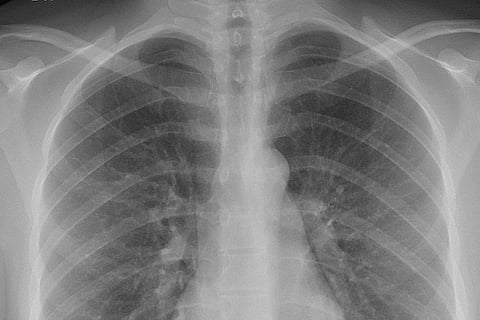

विश्व रेडियोग्राफी दिवस 2023 का विषय "रोगी सुरक्षा का जश्न" है। यह विषय स्वास्थ्य देखभाल प्रणालियों की प्रभावशीलता को बनाए रखने और रोगियों की भलाई सुनिश्चित करने में पेशेवरों द्वारा निभाई जाने वाली महत्वपूर्ण भूमिका पर प्रकाश डालता है, जो विकिरण सुरक्षा के क्षेत्र से आगे तक फैली हुई है।

विश्व रेडियोग्राफी दिवस महत्वपूर्ण है क्योंकि यह उच्च गुणवत्ता, सुरक्षित स्वास्थ्य सेवा प्रदान करने में मेडिकल इमेजिंग पेशेवरों और रेडियोग्राफरों की महत्वपूर्ण भूमिका को पहचान देता है और उसका जश्न मनाता है। यह विकिरण सुरक्षा, रोगी सुरक्षा और स्वास्थ्य देखभाल प्रणालियों की प्रभावशीलता को बनाए रखने में उनके महत्व पर ध्यान आकर्षित करता है।